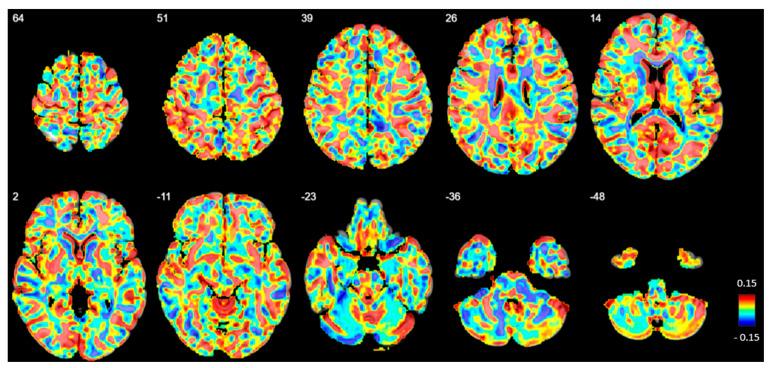

以往的神经影像学研究报告称,边缘型人格障碍(BPD)患者存在大脑结构改变以及局部网络过度兴奋,表现为慢波脑电图(EEG)活动增加。特别是,间歇性节律性δ波和θ波活动(IRDA/IRTA)因其与代谢失衡、神经元应激和情绪调节失调(这些过程与BPD高度相关)的联系,在心理健康领域引起了关注。这些功能障碍可能反映在相应的大脑结构变化中。本研究调查了BPD患者的皮质厚度和皮质下体积,并检查了它们与每分钟IRDA/IRTA事件、症状严重程度和神经心理学测量指标之间的关联。

纳入了70名女性BPD患者和36名年龄匹配的女性健康对照者(HC)(为进行临床EEG比较,甚至有72名患者可用)。使用自动独立成分分析(ICA)方法评估IRDA/IRTA发生率。使用MAGNETOM Prisma 3T系统获取T1加权MRI数据,并使用FreeSurfer(7.2版)分析皮质下结构,使用CAT12分析皮质厚度和总体积测量。心理测量评估包括诸如边缘型症状清单(BSL - 23)和人格组织问卷(IPO)等问卷。使用注意力表现测试(TAP)、文化公平智力测试(CFT - 20 - R)和言语学习与记忆测试(VLMT)评估神经心理学表现。

组间比较显示,BPD组和HC组之间的IRDA/IRTA发生率或结构异常没有显著增加。然而,在BPD组内,扣带回右峡部的皮质厚度与IRDA/IRTA差异(过度换气后减去过度换气前,HV;<0.001)呈负相关。此外,BPD症状严重程度(BSL - 23)和IPO得分与右喙状前扣带回皮质厚度呈正相关(<0.001),IPO得分与右颞极厚度相关(<0.001)。内在警觉性(TAP)与相对小脑体积显著相关(0.01)。

虽然未观察到组水平的结构异常,但EEG减慢、BPD症状严重程度以及警觉性与皮质厚度和/或皮质下体积之间的相关性表明,前扣带回皮质、颞极和小脑在BPD的情绪调节和认知功能中可能发挥潜在作用。未来采用多模态EEG - MRI方法的研究可能会更深入地了解BPD潜在的神经机制,并指导个性化治疗策略。